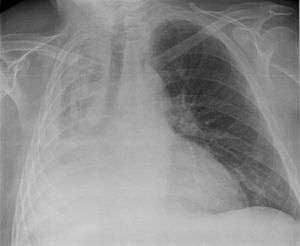

Atelectasis of a person's right lung | |

Atelectasis is the collapse or closure of a lung resulting in reduced or absent gas exchange. It may affect part or all of a lung.[1] It is usually not bilateral. It is a condition where the alveoli are deflated down to little or no volume, as distinct from pulmonary consolidation, in which they are filled with liquid. It is often called a collapsed lung, although that term may also refer to pneumothorax.[2]

- chest X-ray

Post-surgical atelectasis will be bibasal in pattern.

It is usually associated with accumulation of blood, fluid, or air within the pleural cavity, which mechanically collapses the lung. This is a frequent occurrence with pleural effusion, caused by congestive heart failure (CHF). Leakage of air into the pleural cavity (pneumothorax) also leads to compression atelectasis.[7]